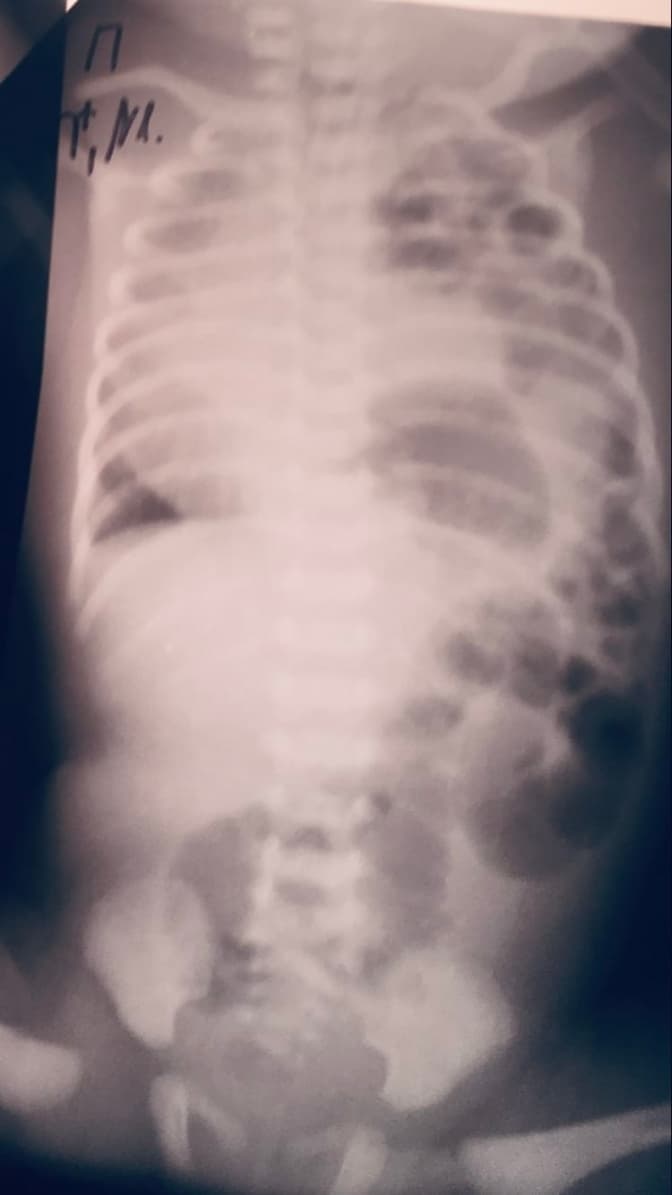

Львівські лікарі ОХМАТДИТу прооперували немовля із важкими вадами. У дитини органи черевної порожнини були у грудній клітці, а серце у правій частині. Про це повідомили на сторінці лікарні у Фейсбуку.

«Трьохденний малюк із Львівщини поступив до нашої лікарні одразу після свого народження із однією із найважчих вад розвитку -– лівобічною діафрагмальною грижею та повністю недорозвиненою лівою легенею», – йдеться у повідомленні.

Після обстеження дитини хірурги виявили повну відсутність одного із куполів діафрагми, що потребувало оперативного втручання з його пластики штучним матеріалом – сіткою, яка відділила органи грудної клітки від органів черевної порожнини. Оперативне втручання тривало 3 години за участю операційної бригади з п'яти спеціалістів.

«Шлунок, кишківник, селезінка, ліва доля печінки розвивалися у лівій половині грудної клітки, що не давало можливості рости лівій легені. Тобто у дитини виражена гіпоплазія лівої легені, а серце – у правій частині грудної клітки. Під час оперативного втручання нам вдалося перемістити черевні органи з грудної клітки туди, де вони мають природньо бути і відділити їх сіткою. Серце почало поступово зміщуватися на своє природнє місце», – коментують в лікарні.

Фото Львівської обласної дитячої клінічної лікарні ОХМАТДИТ